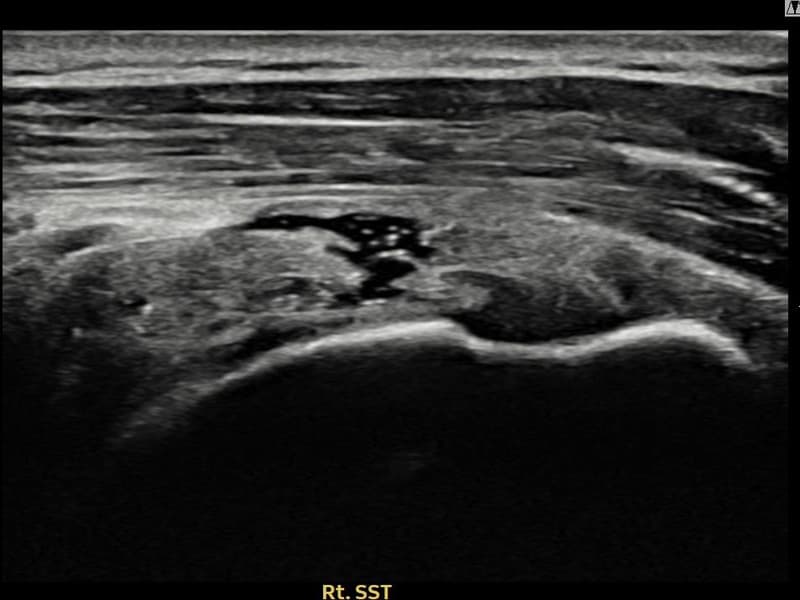

Before

시술 전 초음파 측정 결과 파열 크기는 9mm × 4mm (힘줄 두께의 약 38% 결손)로 확인되었습니다. 시술 전 초음파에서 우측 극상근건 내 에코 단절과 함께 건내 고에코 석회화 소견이 동반 확인되었습니다. 시술 후 초음파에서 파열 부위의 연속성이 회복되고 석회화 부위의 에코 패턴이 개선된 것이 관찰되었습니다.

50대 후반 여성 환자분으로, 야간 통증이 극심하여 어깨를 아래로 향하고 자도 통증이 느껴지는 상태로 내원하셨습니다. 초음파 검사에서 극상근건 부분파열과 함께 건내 석회화가 동반된 복합 소견이 확인되었습니다. 석회화와 파열이 함께 존재하는 경우 충격파만으로는 힘줄 구조 회복이 어려워 초음파 유도 하 축소봉합술을 선택하였습니다. 시술은 30여 분에 완료되었고 당일 귀가 가능하셨으며, 이후 보조기를 착용하며 단계적 재활을 진행하였습니다. 시술 11주 후 추적 초음파에서 파열 부위 연속성 회복과 함께 석회화 소견도 뚜렷이 감소한 것이 확인되어 야간 통증 없이 정상 생활에 복귀하셨습니다.